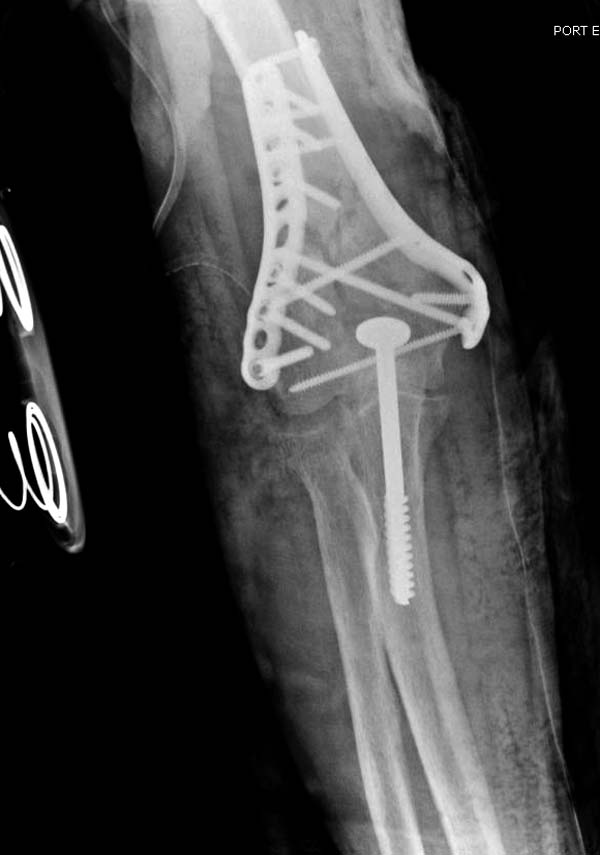

Разработаны различные концепции установки пластин на дистальное плечо:

две параллельные в 180 или под углом в 90 градусов. Почти все компании

имеют все варианты пластинок, а Acumed признает так называемую Keystone

concept  http://www.acumed.net/distal-humerus-plates

Примеры: первому более 15 лет фиксирован шурупом и tension band

technique, а второй перелом открытый больной 80 лет, после наружного

фиксатора в первом этапе и окончательная фиксация вторично. Третьий раз

внесуставная остеотомия...

Имя     : 13 Humerus prox distal.jpg

Тип     : image/jpeg

Размер  : 58399 байтов

Описание: отсутствует

Url     : http://weborto.net:8080/pipermail/ortho/attachments/20130604/c45a379f/attachment-0036.jpg